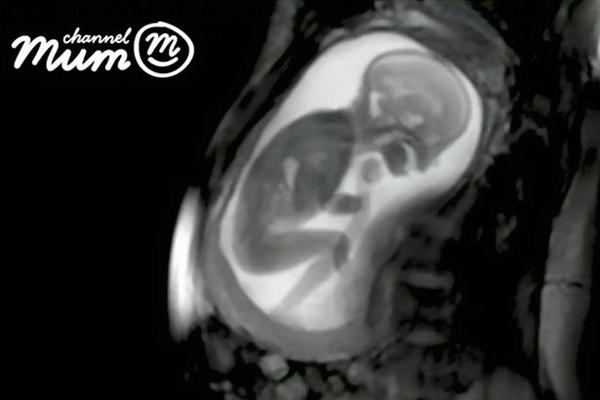

Trong đoạn video kéo dài 20 giây, hình ảnh thai nhi đang nghịch dây rốn, xoay đầu từ bên này sang bên kia, co duỗi người được thể hiện khá rõ nét. Ở những giây kết thúc, em bé thậm chí còn co người đạp mẹ một cái khá mạnh khiến bụng biến dạng.

Hình ảnh em bé đang nghịch dây rốn được chụp lại rõ ràng.